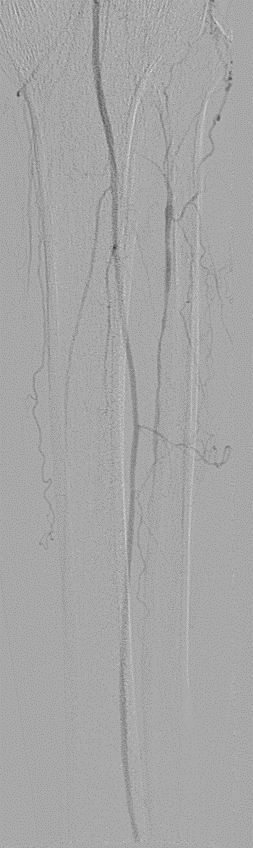

★ Case 3

左右滑动查看

★ Case 4

★ Case 5

Female,82 y

Severe claudication over 1 year in both extremities esp. in the left

DM over 10 years

CTA:SFA-PA long CTO